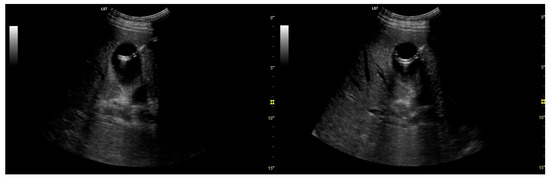

Background: After a failed endoscopic retrograde cholangiopancreatography (ERCP) for malignant biliary obstruction (MBO), second-line drainage is performed with endoscopic ultrasound-guided biliary drainage (EUS-BD) or percutaneous transhepatic biliary drainage (PTBD). We compared their effectiveness, safety, and short-term survival. Methods: We conducted a single-center retrospective cohort of 101 adults with MBO after they had experienced a failed ERCP (EUS-BD n = 37; PTBD n = 64). Allocation was non-randomized and driven by operational availability. Baseline laboratory tests (complete blood count, platelets, and C-reactive protein) and derived indices (neutrophil-to-lymphocyte ratio [NLR], platelet-to-lymphocyte ratio [PLR], lymphocyte-to-monocyte ratio [LMR], systemic immune-inflammation index [SII], systemic inflammation response index [SIRI], neutrophil-to-platelet score [NPS], and lymphocyte-to-CRP ratio [LCR]) were compared. Outcomes that were a technical success include: an early biochemical response (bilirubin reduction), complications (Clavien–Dindo), length of stay (LOS), and overall survival (OS). Between-group comparisons used the two-sided Mann–Whitney U test (continuous) and Fisher’s exact (binary) test. Survival was assessed by the Kaplan–Meier estimator using log-rank testing. To address later adoption of EUS-BD, we also estimated a restricted mean survival time of 180 days (RMST_0–180) with 95% confidence intervals (CIs). Results: Baseline inflammatory markers and composite indices were similar; baseline total bilirubin was higher in PTBD. The technical success was 100% in both groups. Early biochemical response was 86.5% after EUS-BD vs. 78.1% after PTBD (p = 0.43). Any complication occurred in 29.7% vs. 12.5% (p = 0.04); major complications (Clavien–Dindo ≥ III) occurred in 10.8% vs. 0% (p = 0.02), respectively; and the LOS did not differ (p = 0.21). OS favored EUS-BD (median 143 vs. 54 days and log-rank p = 0.012). RMST_0–180 was 111.1 days for EUS-BD vs. 71.4 days for PTBD (difference + 39.6 days; 95% CI 11.3–65.9). Conclusions: After a failed ERCP for MBO, EUS-BD and PTBD achieved universal technical success and similar early biochemical responses, but EUS-BD was associated with higher complication rates and a significantly longer six-month survival. These findings support the individualized selection balancing procedural risk with the anticipated survival benefit and highlight the need for prospective comparative studies. Full article

Show Figures

Figure 1